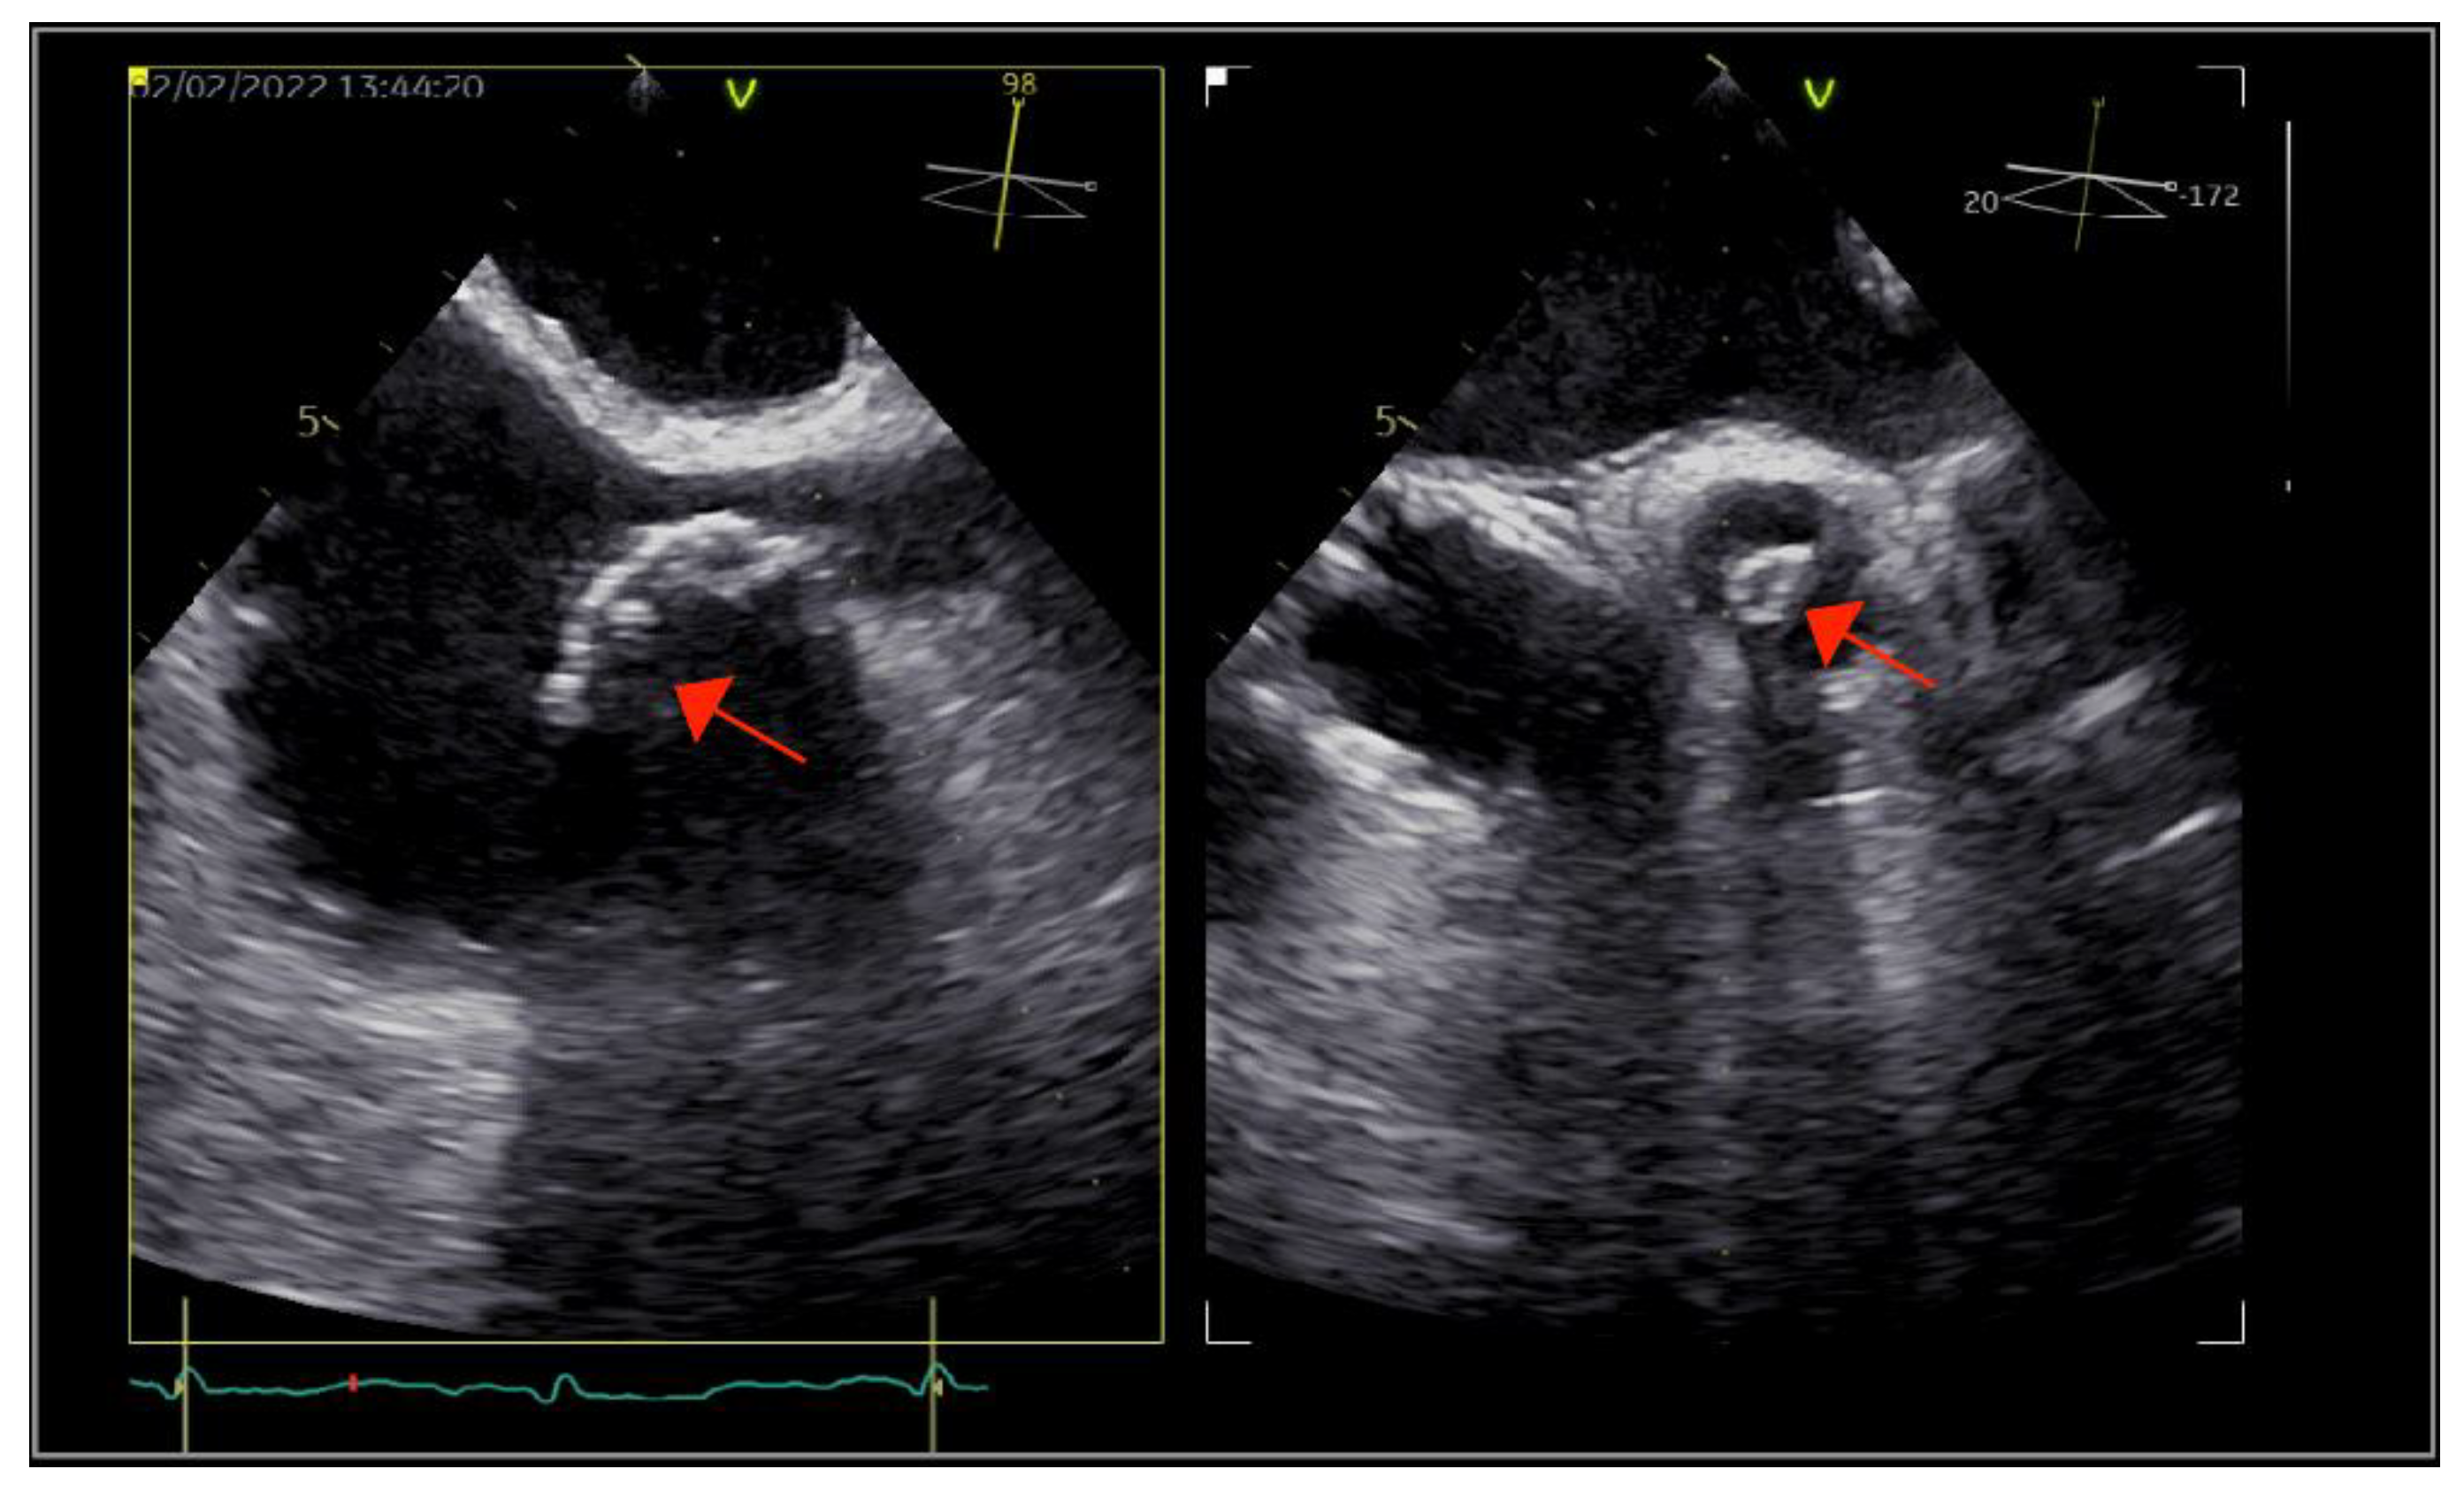

The patient underwent transthoracic echocardiography, which revealed severe aortic and tricuspid regurgitation, moderately reduced left ventricular ejection fraction (35%) and preserved right ventricular systolic function. There were multiple small mobile masses attached to the aortic valve, indicating vegetations. Because the tricuspid valve was thickened, tricuspid endocarditis was also suspected. These findings were corroborated by transesophageal echocardiography (TOE), which revealed multiple vegetations at the level of both the aortic and tricuspid valves that were better visualized with three-dimensional acquisitions (Figure 1). There were no paravalvular complications. Furthermore, TOE visualized an inhomogeneous mass at the level of the superior vena cava (SVC), prolapsing into the right atrium, indicating the possibility of a fibrin sheath subsequent to the removal of the CVC or thrombus (Figure 2).

Figure 1. Transesophageal echocardiography: (A) bi- and tri-dimensional acquisitions depicting multiple vegetations on the tricuspid valve (arrow) and (B) long-axis view showing the aortic valve with vegetations (arrow) and the severe aortic regurgitation. The left aortic coronary cusp was perforated, which was later confirmed during surgery.